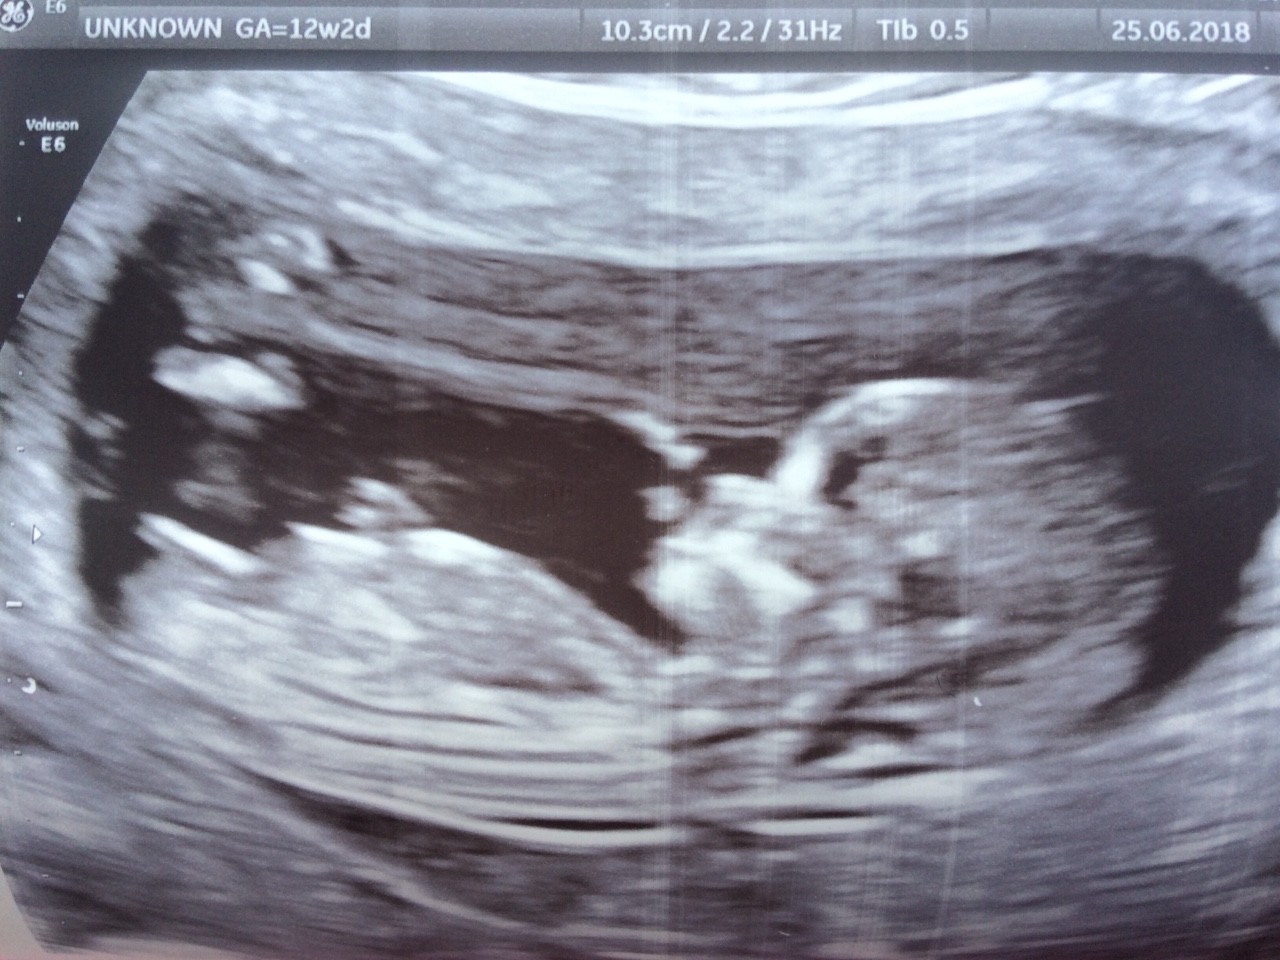

I ja po wizycie. Złe przeczucia sie nie sprawdzily, bo wszystko bardzo dobrze :) maluszek ma juz 2,5cm :) 18 lipca idę na usg prenatalne. Tak sie prezentuje mój dzidz: Zobacz załącznik 870800